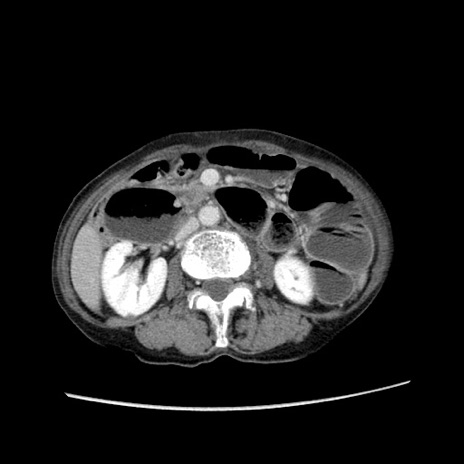

冠状断像

【症例】80歳代女性

【主訴】胸のつかえ感

【現病歴】約9時間前に食後から胸のつかえた感じあり、嘔吐あり、来院。

【既往歴】胃癌(全摘)、胆摘、虫垂炎

【身体所見】心窩部に圧痛あり、反跳痛なし。

【データ】WBC 5700、CRP 0.05